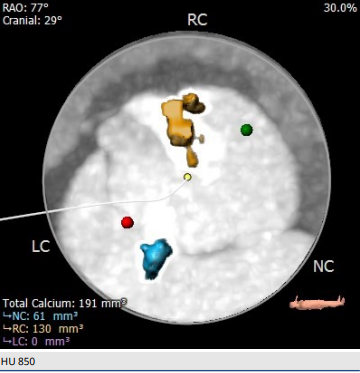

钙化分析

术前陈晓敏教授带领团队对这位患者进行了详细的分析,从CT分析结果显示,患者主动脉瓣为type 0型二叶瓣,瓣环直径为24.4mm,结合患者瓣叶钙化等情况,符合美敦力Evolut PRO 29mm瓣膜选型。经讨论决定以右侧股动脉为主入路,左侧股动脉为辅入路,术中进行23mm球囊预扩张,保证系统顺利跨瓣及释放,并采用世界先进的Cusp Overlap技术植入瓣膜 ,以更精准地释放瓣膜深,减少对患者传导系统的影响。